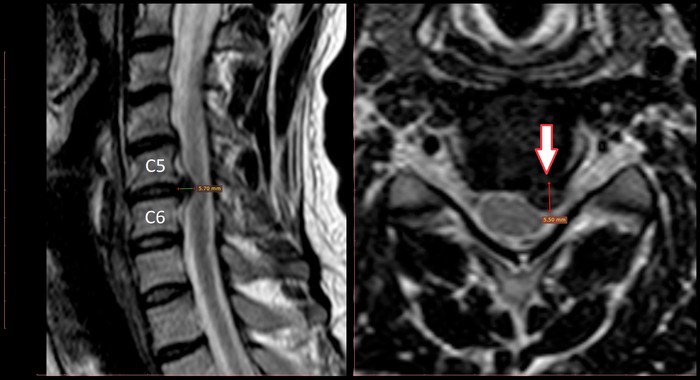

Боль в плече из-за грыжи диска.

Пациенты часто предъявляют жалобы на боль в плече и потом несколько месяцев занимаются его лечением, которое не приводит к желаемому результату. Пробуют физиопроцедуры, блокады с кортикостероидами, НПВС, ЛФК.

И вроде как-бы помогает, но ненадолго и потом все опять возвращается.

• Лекарства, которые используются в лечении, снижают уровень воспаления и облегчают боль, в том числе, если она идет от грыжи диска.

Откуда боль плече?

• Имитировать боль в плече может и межпозвонковая грыжа. Клинический пример – грыжа С5-6 слева, 5,5 мм. Жалобы на боль в области плеча, дискомфорт при повороте шеи.

• Зона иннервации С5-6 как раз находится в области плеча

• В данном случае все лечение должно быть направлено на главную виновницу торжества – грыжу диска.

• Несмотря на ее размер и заверения некоторых врачей, что в этом случае показана хирургическая операция – это не так. В данном клиническом примере нужно пробовать обойтись без нее и добиться уменьшения размеров грыжи.

• Как только размер ее уменьшиться, уйдут и жалобы.